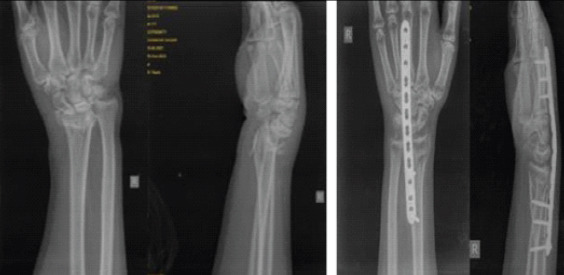

Abstract Image